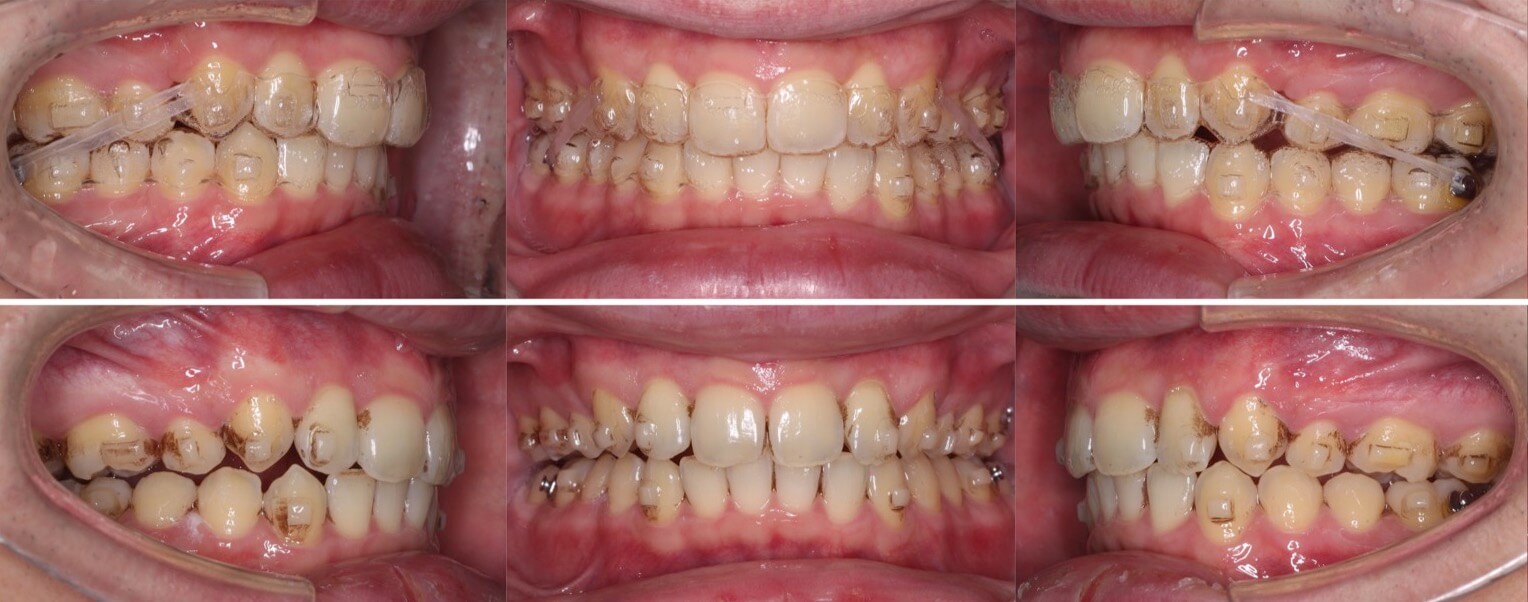

小学生女子・1期治療

<症例概要>

主訴:噛み合わせが深い

年齢・性別:8歳女子

住まい:千葉県八千代市

症状:過蓋咬合・上顎前突

治療方針:上顎前歯圧下・下顎前歯前方傾斜

治療装置:機能的マウスピース矯正装置(プレオルソ)

管理期間:2年6か月

リテーナー:なし

治療費用:484,000(税別)

代表的副作用:痛み・治療後の後戻り・成長による変化

▶︎その他の副作用

下の前が完全に見えない過蓋咬合です。口呼吸も併発しており口唇の突出も見られます。このようなケースは機能的改善効果もある機能的マウスピース矯正装置(プレオルソ)が効果を発揮します。前歯の噛み合わせ改善後も使用頻度を落としながらは使用し続ける事で、正しい位置に生え変わります。口唇に筋力がつき、横顔も引き締まりました。